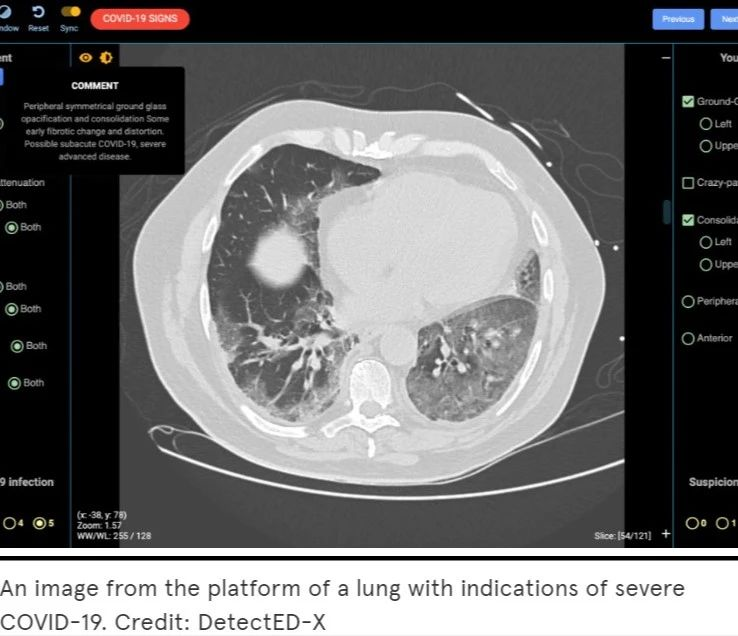

尽早诊断新型冠状肺炎对早期治疗和隔离至关重要。目前,肺部CT已被证明是诊断新型冠状肺炎的首要工具,但医生的CT读片技能可能需要长年累月的经验积累。由DetectED-X开发的名为CovED的辅助测试工具将帮助现有的医生及相关工作人员更快、更准确地诊断病例,并为更多有需要的人员及机构提供快速培训,从而获得完备的CT读片技能,其定制化的培训模块只需要1-2小时就可以生成。

CovED是一个全网开放且免费的平台,得到了全球医疗专家和领先企业的支持。借助CovED,临床医生可以通过真实的CT图像进行虚拟诊断并得到即时的反馈,查看虚拟诊断中产生的所有错误。系统还会按照业界标准为其打分,以此帮助使用者评估自身表现。随着时间的推移,诊断难度也会相应增加。

感染COVID-19 CT图

目前,CovED平台上使用的是来自澳大利亚和欧洲合作者的新型冠状肺炎病例的CT图像。“WHO呼吁全球团结起来应对COVID-19,我们非常感谢合作伙伴GE 医疗、Volpara、世界继续教育联盟(WCEA)和亚马逊的支持,使这个世界级的平台能被建立起来,并快速响应新型冠状肺炎的疫情发展。” Brennan教授说。